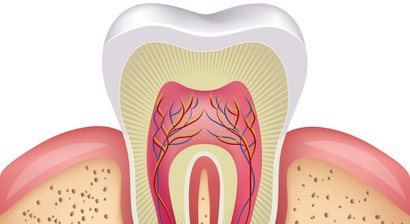

Wurzelbehandlung

Eine Wurzelbehandlung wird dann notwendig, wenn das Innere des Zahnes durch Bakterien erkrankt oder bereits abgestorben ist. Die Aufbereitung des Wurzelkanals erfolgt maschinell unter optischer Vergrößerung (Lupenbrille). Zur genauen Längenbestimmung des Kanals wird zuvor eine elektr...